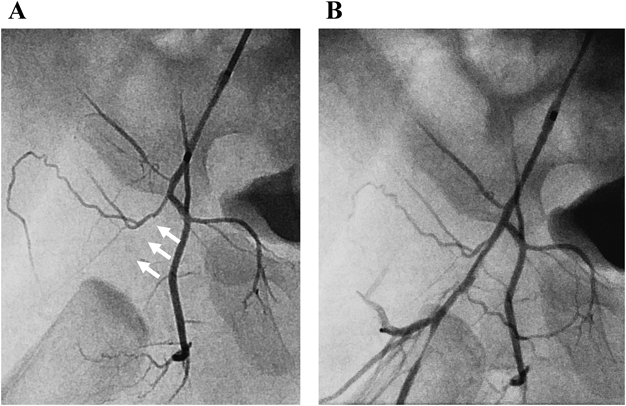

症例4は,心エコー検査にて,PA/IVS,右室低形成,SCの発達が著明と診断されていた.プロスタグランジン製剤の持続投与で管理し,心房間交通の狭小化のため,日齢22にstatic BASを行った.その際の冠動脈造影で,LAD離断とSCからの側副血行路を認めた.また,static BAS中に心電図上,II・III・aVF誘導で一過性にST上昇が出現し,右室流入血流の減少による冠還流低下が原因と考えられた.加えて,啼泣時にショックをきたした既往もあり,顕著な右室依存性冠循環(Right ventricle dependent coronary circulation: RVDCC)が示唆された.これらの所見から,周術期の心筋虚血のリスクが高いと判断し,初回の姑息的治療としてDSを選択した.日齢53,体重3.1 kgでDSを施行した.本症例の動脈管は大動脈弓遠位部からやや横走する形態であり,右大腿動脈アプローチとした.Parent Plus 30®(メディキット株式会社;東京)から,LEONIS Mova HF™(住友ベークライト;東京)と0.014 inch GT wire™(テルモ株式会社;東京)で動脈管を通過し肺動脈に到達した.その後0.014 inch Flexi wire™(Boston Scientific; Malborough, MA)に入れ替え,主肺動脈内で反転した状態で安定させ,MULTI-LINK 8® 3.0×18.0 mmを留置し21 atm(3.4 mm)まで後拡張した.確認造影で,ステントは若干肺動脈側に偏位していたものの,肺動脈の狭窄を認めず手技を終了した(Fig. 6).DS後,高肺血流性心不全は軽度でSpO2 85%程度で安定していたが,右大腿動脈触知不良を認めていた.DS後3週間ほどで,上気道炎を契機にSpO2が70%台に低下し,心エコーで新生内膜肥厚によると思われる,軽度のステント内狭窄(In-stent restenosis; ISR)を認めたため,日齢71,体重3.5 kgでステント追加の方針とした.確認造影で,前回留置したステント位置はISRに伴い前方への偏位が自然に是正され適正化していた.左大腿動脈からアプローチし,MULTI-LINK 8® 4.0×15.0 mmを留置し,大動脈側15 atm(4.39 mm),肺動脈側12 atm(4.0 mm)で後拡張した.その後,右大腿動脈の閉塞を確認したため,0.014 inch ACSハイトルクバランスガイドワイヤー™(Abbott; Chicago, IL)で開通後にRX Trek 2.0×15.0 mm™(Abbott; Chicago, IL)で順次拡張した(Fig. 7).DS追加後,高度の高肺血流性心不全を認め,ドブタミン塩酸塩,ミルリノン,アンギオテンシン変換酵素阻害薬,ジゴキシンによる心不全治療を必要とした.心不全は徐々に改善しSpO2 80%前半で安定し,体重増加も順調となったが,心エコーで心内膜下の輝度上昇や腹部血管の虚血所見を認め,高肺血流の影響が疑われたため,生後3か月,体重4.4 kgで心臓カテーテル検査を施行した.肺体血流比1.08と肺血流の増加はなく,肺血管抵抗2.8 units·m2と許容範囲であったものの,大動脈圧95/23(48) mmHgと脈圧の増大があり,冠動脈血流に懸念が残るため,カテーテル検査から5日後に両方向性Glenn手術を施行した.術後経過は良好で,心内膜の輝度上昇も改善し,術後3週間で退院となった.

Pediatric Cardiology and Cardiac Surgery 36(4): 294-305 (2020)

Fig. 7 Percutaneous transluminal angioplasty for the right femoral artery

A) White arrows show the occluded right femoral artery at the puncture point of the previous procedure. B) Recanalized right femoral artery.